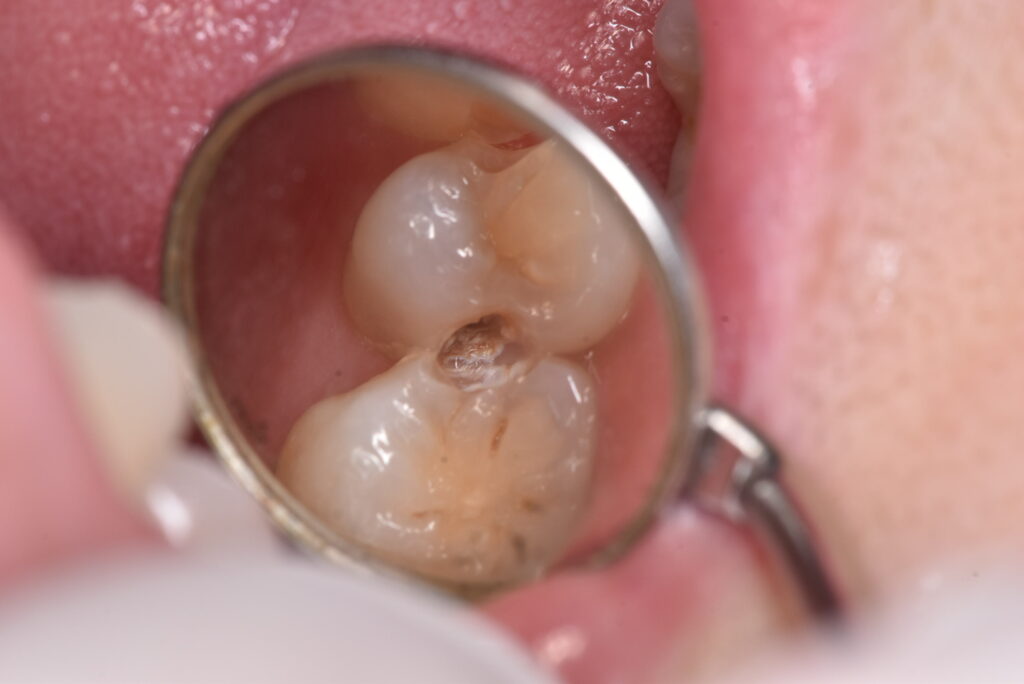

間の部分にむし歯があるのですが、おわかりでしょうか?「なにもないよ!」と言う方の方が多いのではないでしょうか?では、ここを削っていったらどうなったのか、下の写真をご覧ください。

神経に到達する寸前くらいの、深いむし歯が広がっていました。これまでのブログでも書いた通り、今回も症状はありません。では、問題なかったのか?でいうと、答えは上の写真に示した通りです。